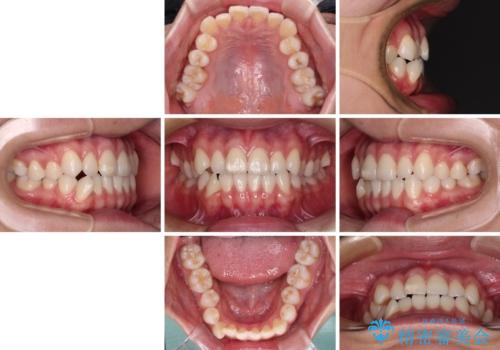

咬み合わせの乱れを改善 ワイヤー装置で楽々矯正治療

- 前歯のデコボコと奥歯の咬み合わせを気にして来院された患者様です。

右側の奥歯は、上が外側に転位した鋏状咬合を呈しており、前歯のデコボコ改善と並行して咬み合わせを改善していく必要がありました。

装置はワイヤー装置でもインビザラインのマウスピースでもどちらでも適用でしたが、自己管理の煩わしさを嫌い、ワイヤー矯正にて治療を行うこととしました。

ワイヤー矯正を選択されたため、鋏状咬合を確実に改善するために補助装置を併用することとしました。

ワイヤー装置でもマウスピースでも、どちらでも適用の症例でしたが、片側の鋏状咬合はマウスピース矯正ではしっかりと改善できる可能性が低いことや、何と言っても自己管理の煩わしさがないことから、ワイヤー装置を選択されました。